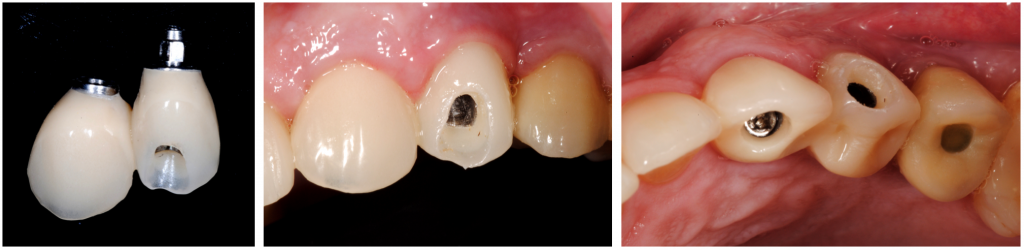

El torque final fue de 50nm, y se optó por hacer carga inmediata no funcional mediante la ferulización del provisional al implante de los dientes 24.

Restauración final

Ocho meses después, se sustituyó la corona provisional por una corona tradicional de circonio, mostrando una sorprendente arquitectura gingival, que se consideró inmutable después de una 6th, 18th, y 24th período de seguimiento del mes.